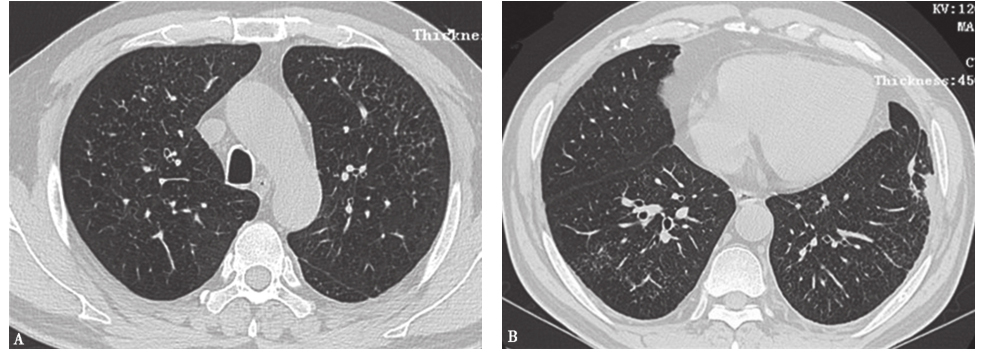

图3肺癌伴肺内转移CT表现

女性患者,45岁,肺癌伴肺内转移。胸部CT见两肺广泛粟粒状小结节影

图4癌性淋巴管炎胸部CT表现

女性患者,55岁,胃癌。胸部CT可见双侧少量胸腔积液伴网格状周边型结节,呈癌性淋巴管炎表现